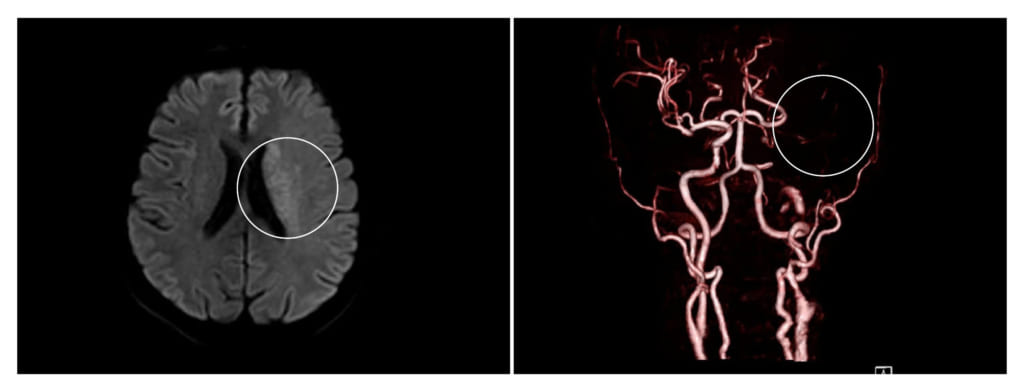

Bệnh nhân nhập viện trong tình trạng liệt nửa người bên phải, mất ngôn ngữ, lơ mơ. Bác sĩ tiến hành thăm khám kiểm tra và chỉ định các cận lâm sàng cần thiết cho bệnh nhân. Kết quả chụp MRI cho thấy bệnh nhân bị đột quỵ nhồi máu não do tắc động mạch cảnh trong bên trái. May mắn là bệnh nhân được đưa đến cấp cứu trong giờ vàng. Vì vậy, bác sĩ tư vấn cho người nhà cần nhanh chóng can thiệp lấy huyết khối khai thông mạch máu đang bị tắc nghẽn.

Khu vực não bị tắc nghẽn của chú B. trên hình chụp máy MRI 3 Tesla (Ảnh: Tuấn Anh)